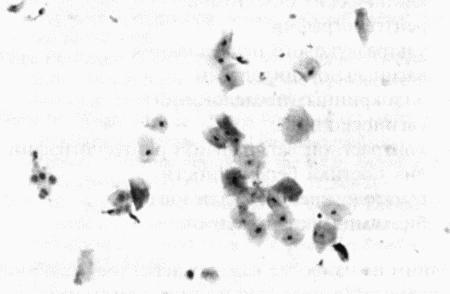

Вагинальная цитология

Повышение концентрации эстрадиола в период проэструса стимулирует деление клеток в базальных слоях вагинального эпителия, но затем концентрация эстрадиола, а соответственно и эндокринная поддержка образования нового, многослойного эпителия снижается, поэтому в образце обнаруживается больше мертвых ороговевших клеток. По мере развития проэструса снижается количество эпителиальных клеток, содержащих ядро. С начала до середины проэструса в вагинальных мазках обнаруживают повышенное содержание эритроцитов. Пик ороговения совпадает с началом повышения концентрации прогестерона; однако в начале эструса исследование не обнаруживает характерных особенностей, которые могли бы указывать на начало фертильного периода. Как правило, такой период наступает несколькими днями позже (табл. 1.1). Тем не менее вагинальная цитология остается популярным методом определения репродуктивного статуса суки из-за своей дешевизны, простоты и доступности. Для получения образца используют ватный тампон, предпочтительно небольшой, который вводят во влагалище и осторожно берут мазок. Полученные клетки помещают под микроскоп, а затем окрашивают контрастным (трихромом) или неконтрастным (например, препаратом Diff-Quik) веществом. При таком окрашивании мертвые кератинизированные клетки становятся оранжевыми, тогда как активные ядерные клетки, а также базальные и парабазальные эпителиальные клетки приобретают различные оттенки от голубого до зеленого.

Ближе к окончанию эструса вагинальные выделения претерпевают характерные изменения (снова выявляются эпителиальные клетки, содержащие ядро, и появляется большое количество лейкоцитов). Такая картина обычно наблюдается через 7–9 дней после пика ЛГ и известна как «вагинальный мазок метэструса». Изменению характера выделений предшествует переходный период, характеризующийся возрастающим количеством активных клеток и указывающий на окончание фертильного периода и эструса (табл. 1.1).

Вагинальная цитология весьма информативна в плане определения фазы эстрального цикла, однако значительные расхождения во времени появления основных признаков эструса по отношению к пику фертильности ограничивает применение указанной методики.